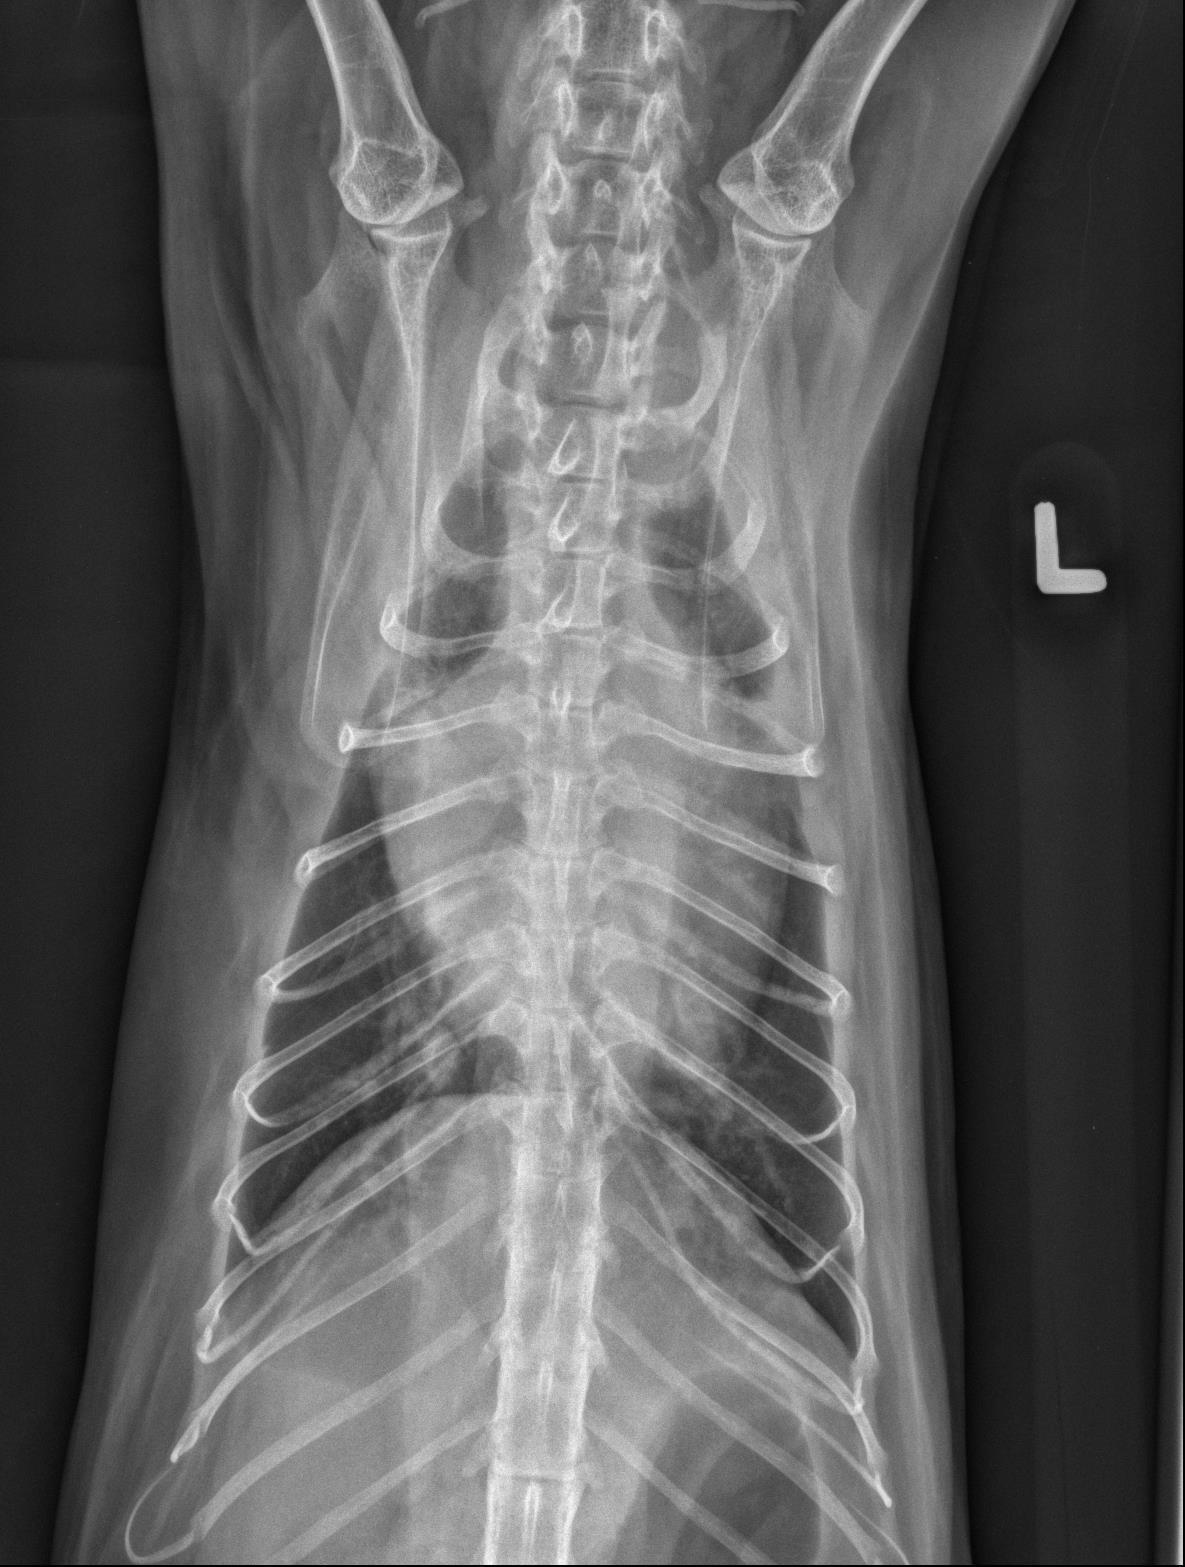

The cardiac silhouette is moderately to severely enlarged occupying greater than 2/3 the height of the thoracic cavity and almost the entire width of the thoracic cavity on the ventrodorsal radiograph. The right cranial lobar pulmonary vein is mildly enlarged compared to the corresponding artery. The pulmonary arteries are enlarged and mildly tortuous. There is a mild, diffuse unstructured interstitial to bronchointerstitial pulmonary pattern.

There is a small volume of fluid in the pleural space of both hemithoraces which widens the pleural fissures. The cranial mediastinum is widened on the ventrodorsal radiograph and there is a focal, rounded, soft tissue opaque convexity immediately dorsal to the second sternebra. There is a small volume of incidental gas within the intrathoracic esophagus.

Severe cardiomegaly in conjunction with the enlarged right cranial lobar vein, pleural effusion and diffuse unstructured interstitial pulmonary pattern is most concerning for congestive heart failure from underlying cardiomyopathy and/or fluid overload. Echocardiography is recommended for further evaluation. The mild tortuosity of the pulmonary arteries may be a patient variant or represent a component of cardiovascular disease (vs. pulmonary hypertension). – The soft tissue convexity immediately dorsal to the second sternebra may represent an enlarged sternal lymph node or loculated pleural effusion.